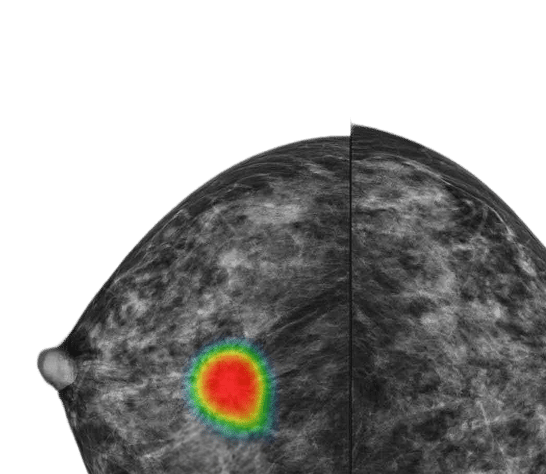

2. Lunit INSIGHT MMG(マンモグラフィ解析)

マンモグラフィ画像から乳がんが疑われる悪性病変(腫瘤、微小石灰化、構造歪曲、局所非対称性陰影)を自動検出するAIモジュールです。96%という驚異的な検出精度を実現しており、疑わしい領域の位置を画像上にマーキングし、悪性度スコアを定量的に提示します。放射線科医の第二読影者として機能し、見逃しリスクを大幅に低減します。特に高濃度乳房(デンスブレスト)における病変検出において、人間の放射線科医単独での読影と比較して有意な精度向上が臨床研究で実証されています。乳がん検診プログラムにおけるダブルリーディングの効率化にも大きく貢献しています。